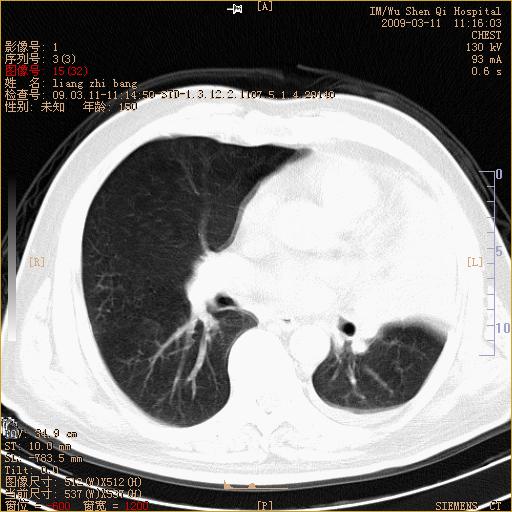

标题: CT18604:男,60岁,咳嗽一月余 [打印本页]

标题: CT18604:男,60岁,咳嗽一月余

1)考虑左肺上叶中央型肺癌并左肺上叶肺不张;建议必要时行纤支镜检查进一步明确诊断。2)左侧胸腔积液。

肺门肿块、支气管开口闭塞伴肺不张及胸水!典型的中心型肺癌变现!

1、左肺上叶中央型肺癌并上叶阻塞性肺不张。

2、左侧胸腔少量积液,右侧胸膜轻度增厚。

左肺们肿块并左肺上叶不张。考虑左肺中心性肺癌并左肺上叶不张及左侧胸腔积液